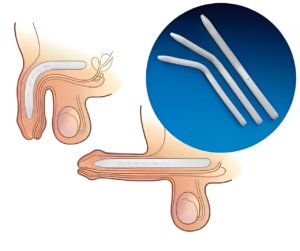

- Prostatectomia Radical:

- Remoção completa da próstata, geralmente indicada para o tratamento do câncer de próstata.

A recuperação varia conforme o tipo de cirurgia. Procedimentos como a RTU e a Enucleção Prostática permitem alta hospitalar no mesmo ou em poucos dias, com retorno rápido às atividades normais. A prostatectomia radical pode exigir uma recuperação mais longa, com acompanhamento contínuo.